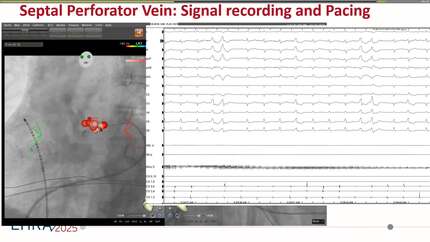

Catheter ablation of left ventricular summit premature ventricular contractions using focal pulsed field ablation within great cardiac vein